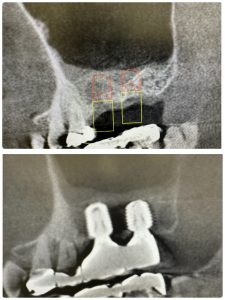

次の喜びは、歯性上顎洞炎

大した病巣ではないが、小さい内に芽を摘む

4か月経過。本日根充

耳鼻科副鼻腔の隣接領域は非常に興味ある

大したインパクトとはないが、嬉しいね